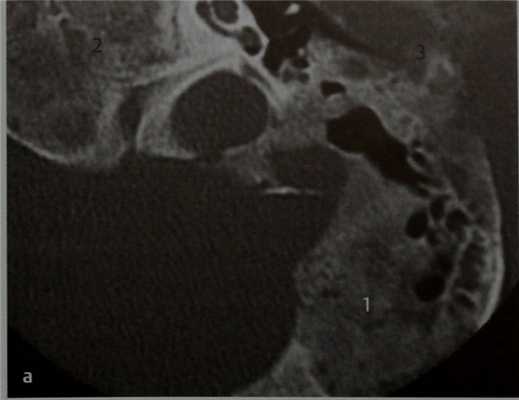

Пациент с синдромом Мак-Кьюна-Олбрайта, обратившийся с жалобами на прогрессирующее снижение слуха.

КТ в горизонтальной проекции. Фиброзная дисплазия характеризуется замещением кости патологической пролиферирующей фиброзной тканью, которое проявляется увеличением объема кости и появлением асимметрии. Фиброзная дисплазия может быть монооссальной, когда поражается лишь одна кость, и полиоссальной, при которой поражается несколько костей (полиоссальная фиброзная дисплазия). У данного пациента с полиоссальной формой фиброзной дисплазии выявлено обширное поражение сосцевидного отростка (7), верхушки пирамиды височной кости (2) и основания передней черепной ямки (3). При поражении области ВНЧС может нарушиться его функция и развиться стеноз наружного слухового прохода.

КТ в вертикальной проекции. Мыщелковый отросток нижней челюсти (1) едва идентифицируется, и контуры средней черепной ямки почти не видны (2), что делает опасным выполнение хирургического вмешательства в згой области. Наружный слуховой проход полностью закрыт (обструкция) (3).